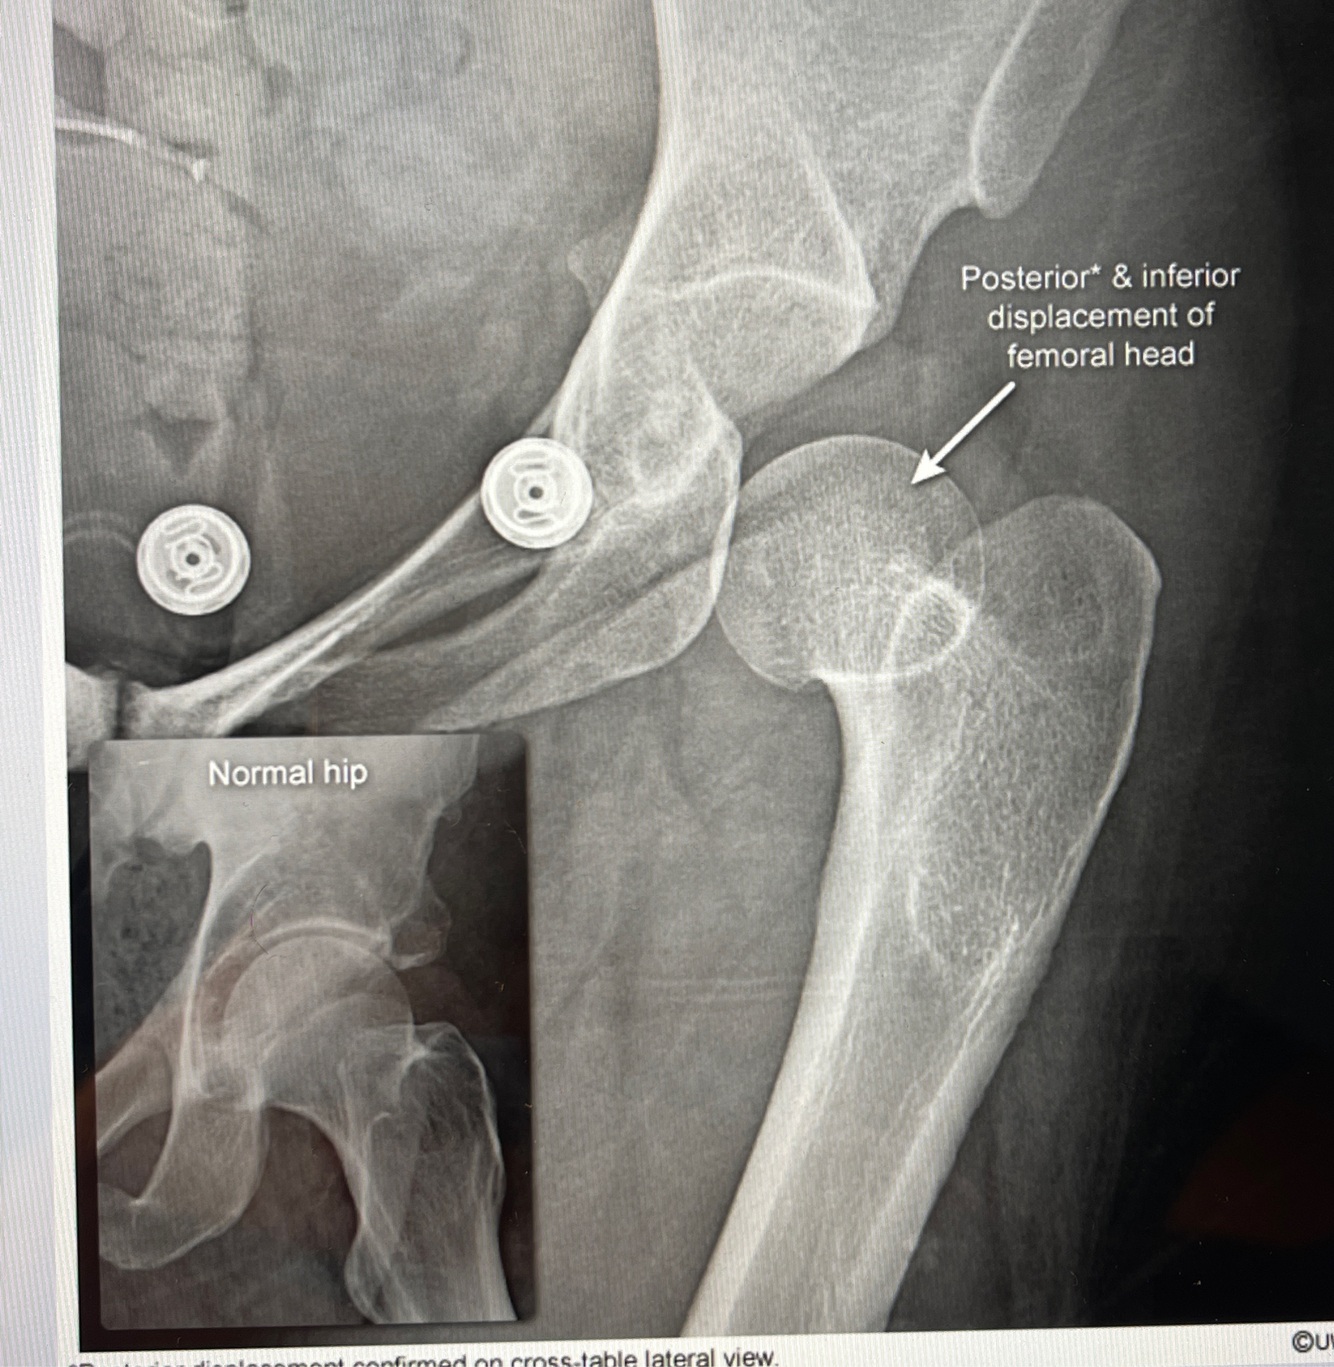

How well did you know this?